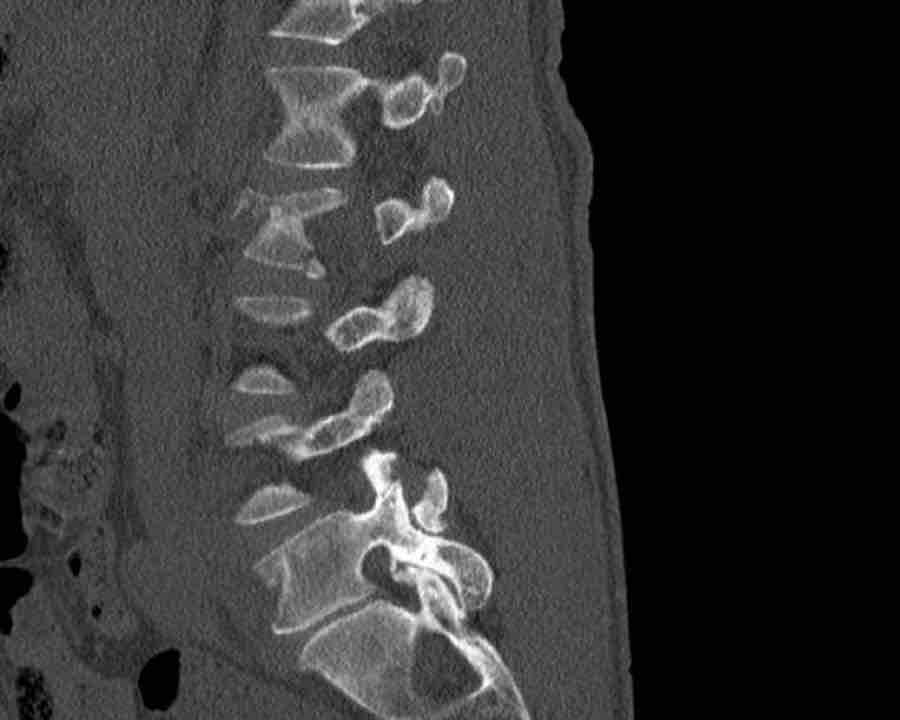

Scroll through the images

Findings:

- Perched facet joints (yellow curved arrows), so think of C injury.

- Posterior displacement of the vertebral bodies in the midline.

- Secondary A4 injury of the vertebral body.

Conclusion

Type C + A4 injury